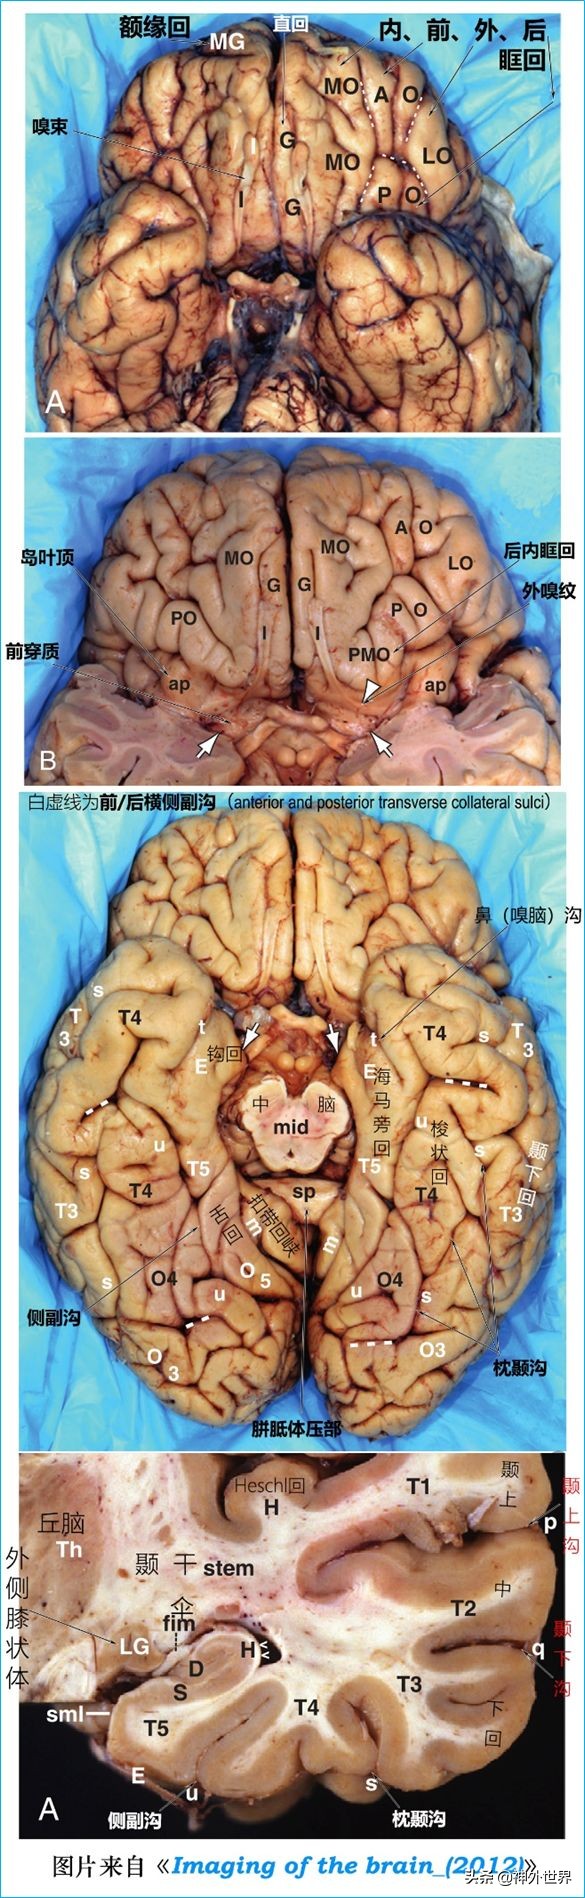

- O4: 枕颞外侧回枕后内部Posterior intraoccipital portion of the LOTG

- O5: 舌回(枕颞内侧回) [Lingual gyrus (medial occipital-temporal gyrus)]

颞叶Temporal lobe

- T1: 颞上回(Superior temporal gyrus)

- T2: 颞中回(Middle temporal gyrus)

- T3: 颞下回(Inferior temporal gyrus)

- T4: 枕颞外侧回颞前内部(Anterior intratemporal portion of the LOTG)

- T5: 海马旁回(Parahippocampal gyrus)

4、大脑半球底面脑沟回定位: